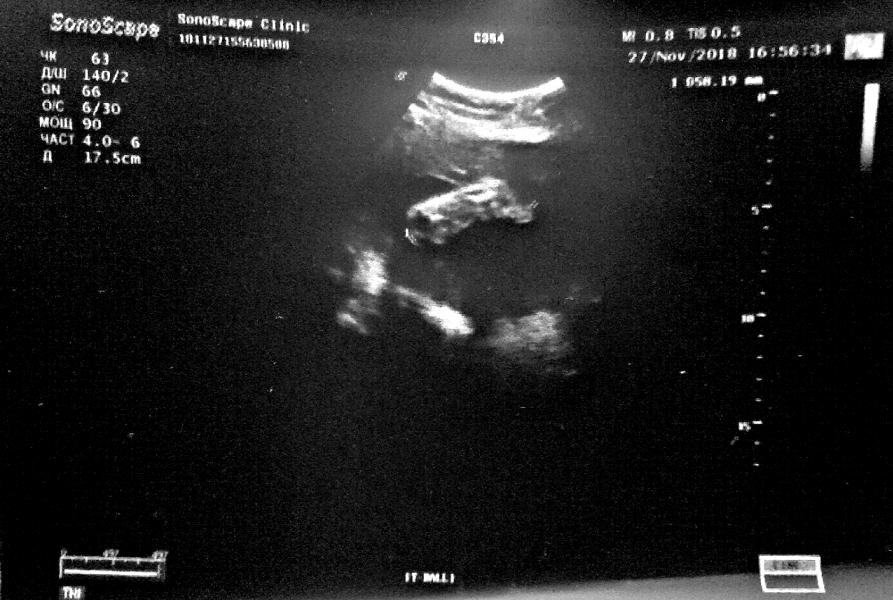

Была недавно на 3 скрининге. Запомнилась... ступня! Она великолепна. У меня 40 размер, у неё будет не меньше. Ещё сказали, что ножки длинные, что тоже умиляет. Узист оглядел нас с мужем и решил, что она в бабушек или дедушек, ибо мы коротконогие. Мне не очень повезло с этим. Брат почти 190 см., отец больше 180, мама чуть ниже отца, а я... чуть больше 160. Если сравнивать с братиком, то самый настоящий лилипут. Интересно, конечно, что и от кого дочь унаследует...